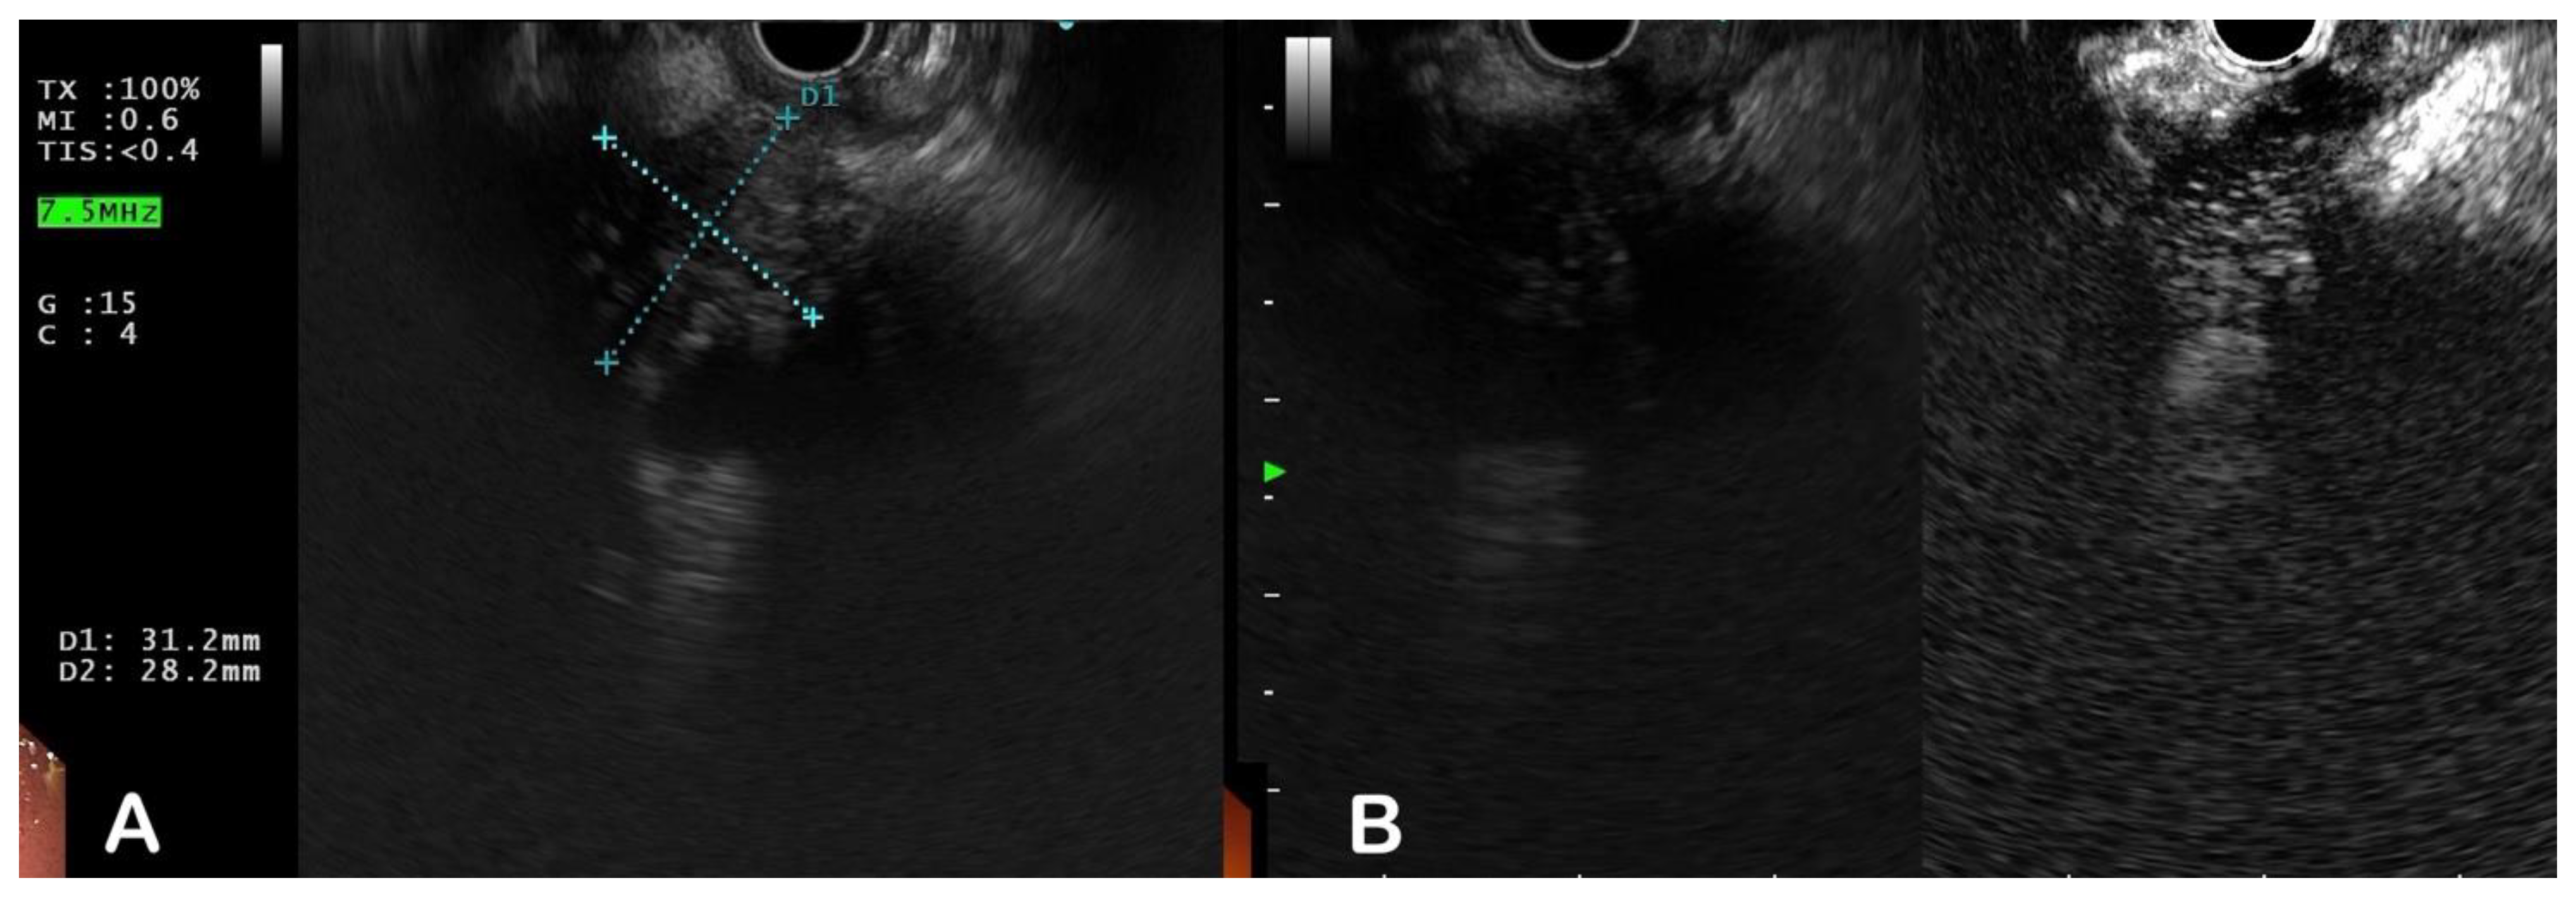

5.3. Endoscopic Modalities

5.4. Other Modalities